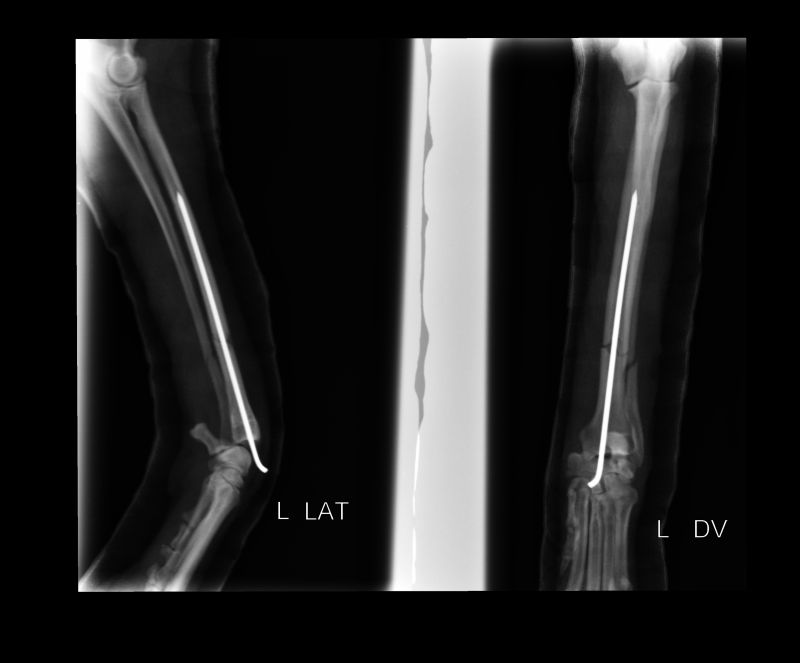

Abnormal Pathology on your pet

Shown on x-ray images which we have taken over the years.

Some interesting patient cases